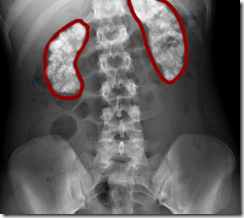

Pemeriksaan BNO Pada kasus kalsifikasi

proyeksi AP pada gambaran diatas sangat jelas menampakan adanya kelainan jenis kalsifikasi pada ginjal kiri, keluhan pasien dengan riwayat sering mengeluh pegal pada pinggang belakang, namun terkadang timbul hilang.

adanya defect pada ginjal kiri

staghorn calsifikasi

nephrocalsinosis